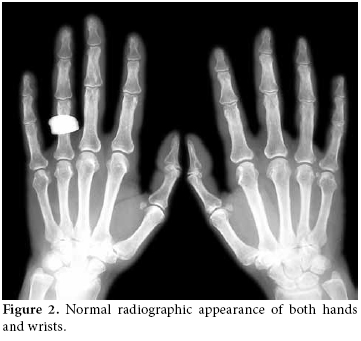

All of the laboratory test values (hemogram, routine biochemistry, C-reactive protein, and rheumatoid factor) were within normal limits. Radiographs of both hands and wrists (figure 2) were also found to be normal. After these results, a three-phase bone scan (Technetium-99m) was obtained. It showed diffuse increased uptake and hyperemia in the right wrist in the first phase, and diffusely increased uptake in the right wrist, metacarpals, and phalanges in the third phase (figure 3). The appearance was scintigraphically compatible with CRPS.

A diagnosis is usually based on clinical appearance and may be supported by other diagnostic methods like radiographic and scintigraphic studies. Radiography typically demonstrates patchy demineralization in the affected part which may be the result of disuse. Three-phase bone scintigraphy shows increased activity in both the blood pool and static phases. A comparison of radiography and bone scintigraphy revealed that bone scans are more sensitive than radiographs, especially in the early phase of the condition[16] as was seen in our case.